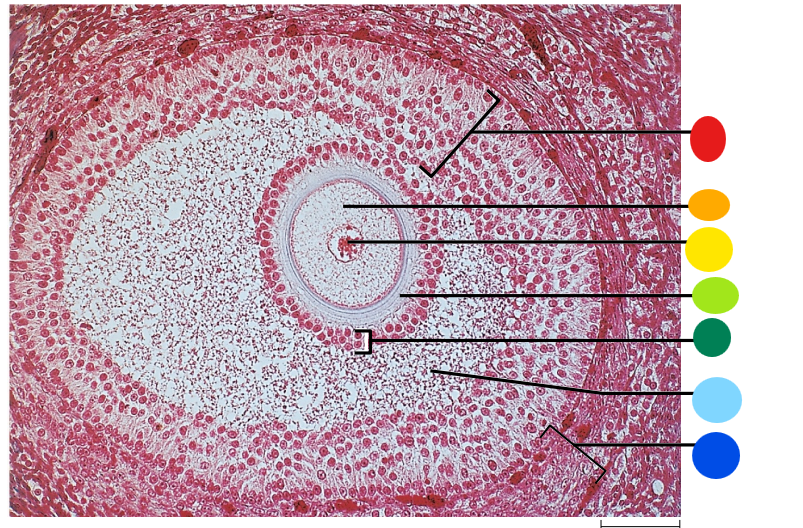

red

tunica albuginea

orange

primordial follicles

yellow

follicular cells

light green

primary oocyte

dark green

granulosa cells

light blue

primary follicles

what is this?

ovary